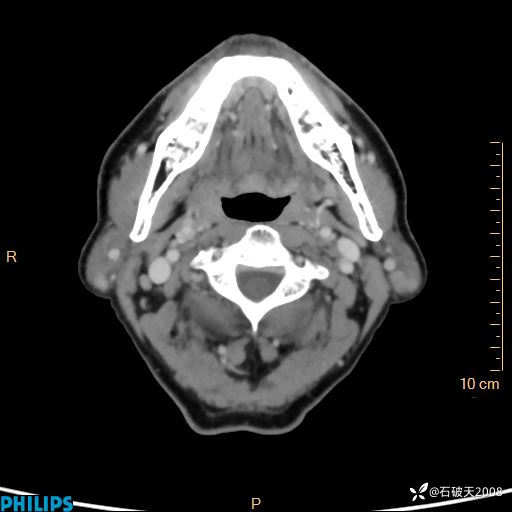

病例分享:老年男性,颈部占位,一周后公布病理

胡志勇HZY 达人已点赞男 61岁 主 诉:发现左侧面部肿物1年余。

现病史:患者于1年余前无意间发现左侧耳下有一肿物,大小如“花生米样”,无压痛,无明显红肿,无畏寒、发热,无咳嗽、咳痰,无盗汗、心慌,无手足颤动、胸闷及性格改变,未在意,未给予特殊处理,2天前至我院行彩超示: 左侧腮腺内低回声(考虑肿大淋巴结),现患者为求进一步诊治,遂来我院就诊,门诊以“局部肿物”为诊断收住我科。自发病来,患者神志清,精神可,饮食睡眠尚可,大小便正常,近期体重无下降。

动脉期